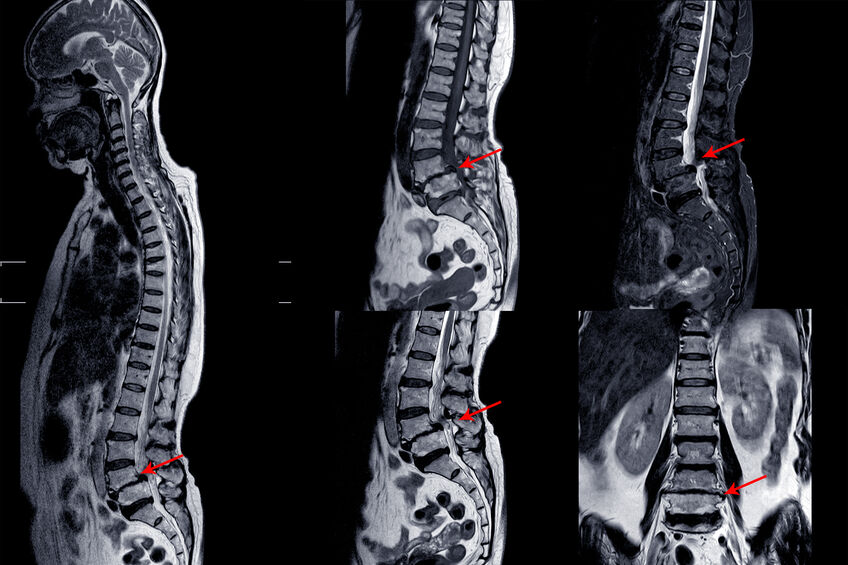

En el caso de la ciática como ya hemos explicado, normalmente lo que están afectadas son las raíces lumbares se precisa de una exploración minuciosa para determinar que raíz está afectada, muchas veces en la resonancia vemos compresión en muchos niveles y es con la exploración como conseguimos determinar cual de los segmentos estenosados está afectado y produce la ciática.

La realización de la resonancia es fundamental para observar con detalle la columna y determinar los niveles afectados, si hay o no mucha degeneración, determinar la presencia de inestabilidades lo que nos ayudara a determinar el tratamiento más oportuno.